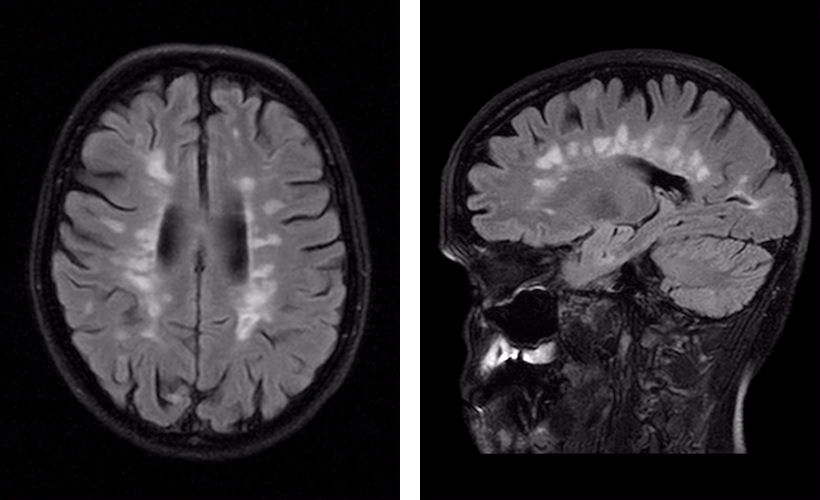

Dawsons fingers